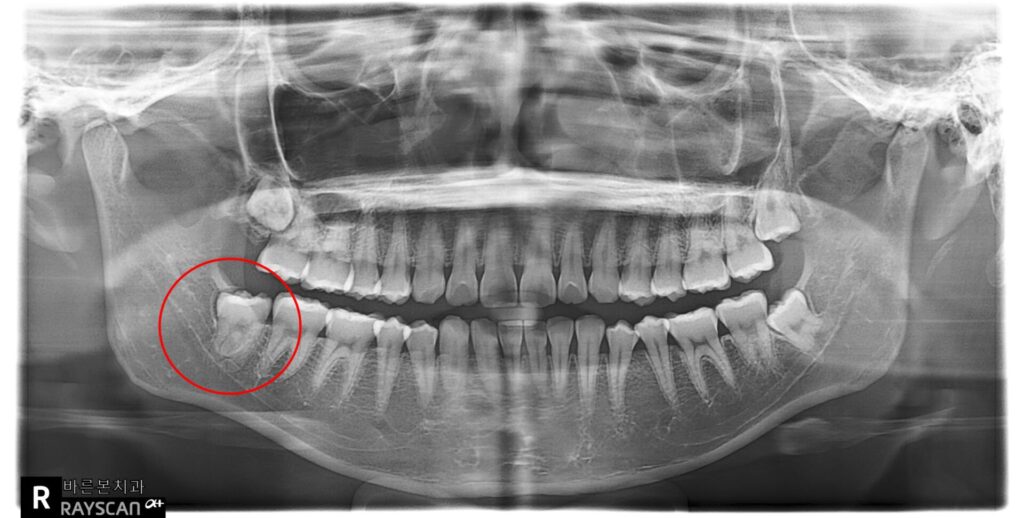

X-ray 사진입니다.

왼쪽 아래 매복사랑니가 보이고

(빨강색동그라미)

사랑니머리가 금으로 씌워진 어금니를

약간 밀고 있는 듯한 모습입니다.